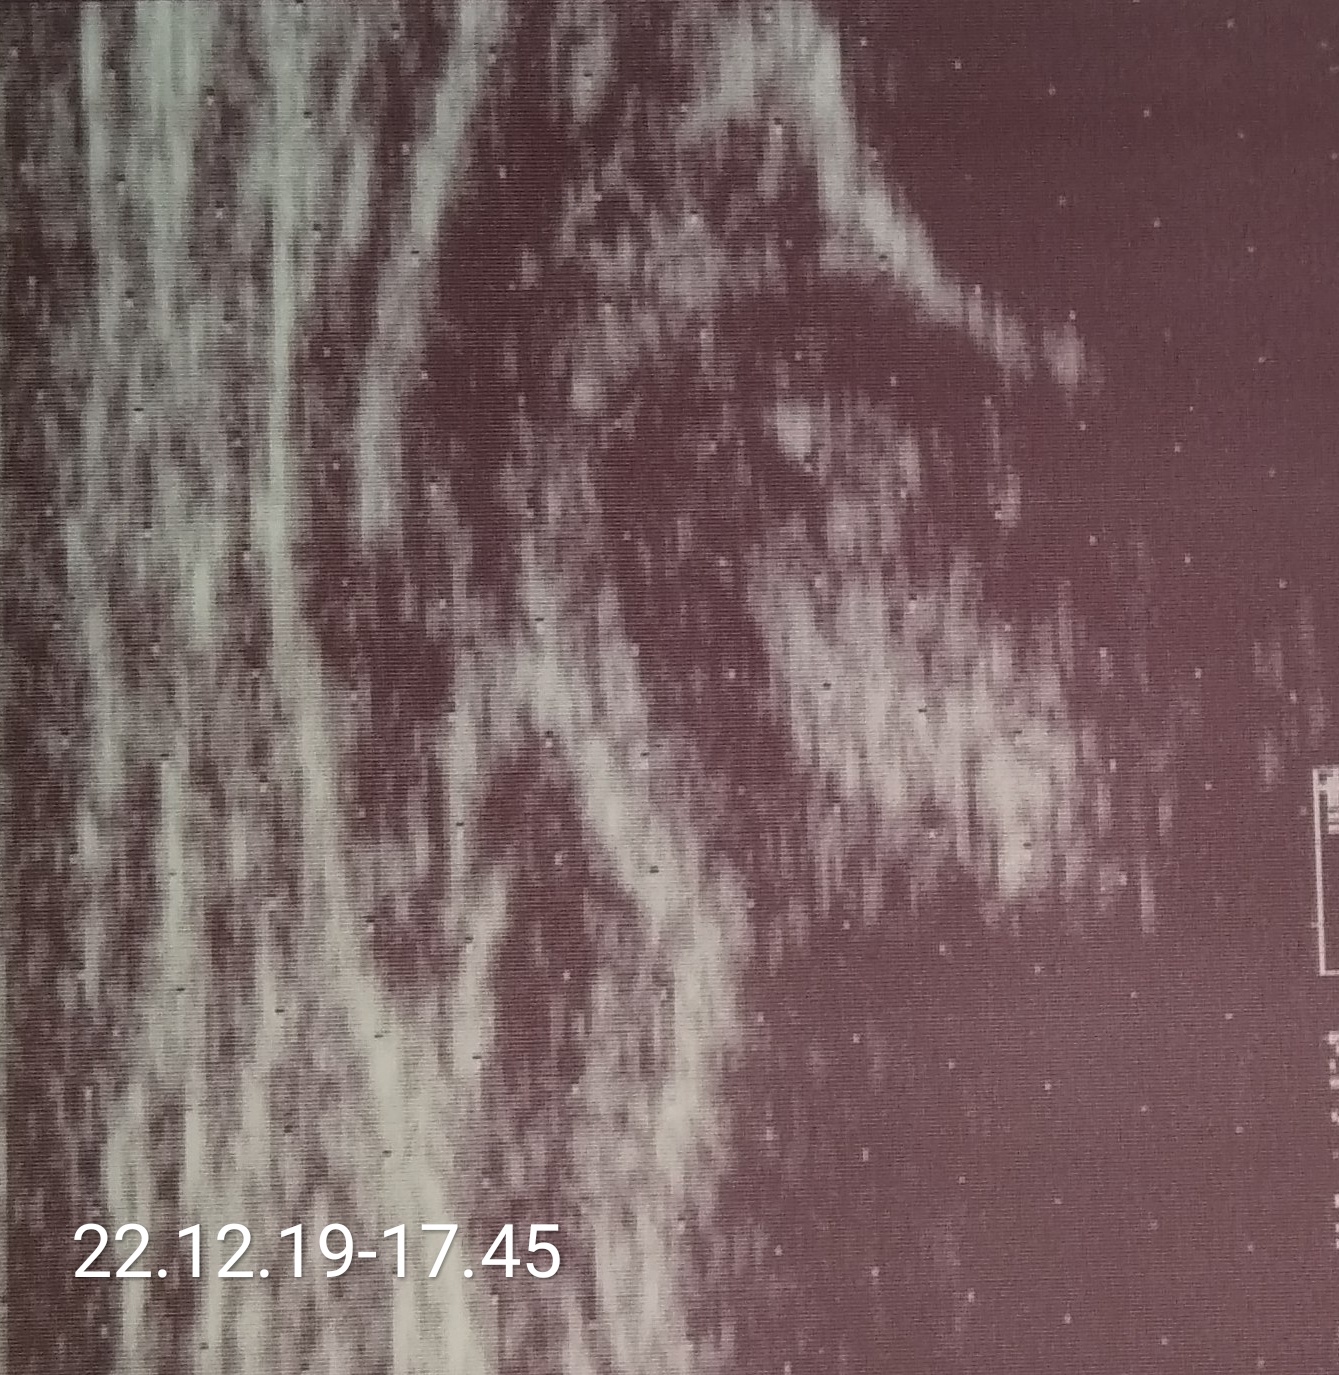

case Natalii typ IV right hip diagnosis 1month; tratment with orthesis wthout effect to 5 month

rehabilitation was ordered ;

slowy increase from 3 time a week to 3 time a day ( 20 minutes each time)

type IIb but unfortunataly unstable becouse with overgrown lig. capitis fem. (big white echo on the right and below side of the femur's head )